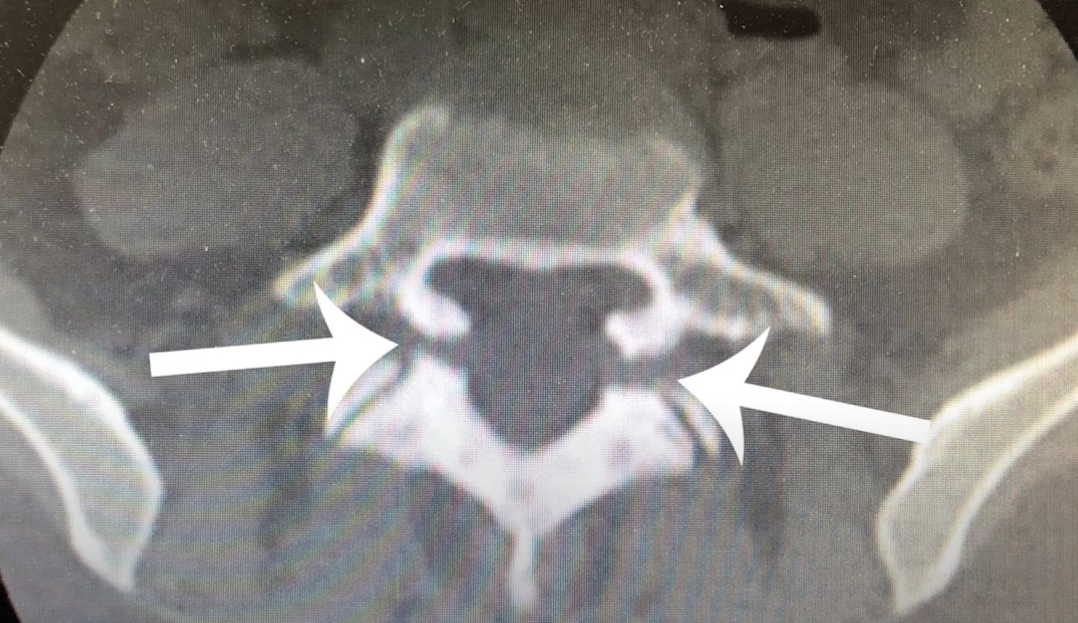

В клинику обратилась пациентка с жалобой на боль в спине и онемение в ноге. У неё были готовые снимки, которые изготавливались в другом медицинском учреждении. Там ей предлагали провести операцию по удалению грыжи. На снимках же был спондилолизный спондилолистез. Чтобы убедиться в этом, выполнили компьютерную томографию. На снимках видно, что присутствует незаращение дуги. Подтверждение диагноза в корне поменяло тактику лечения, потому что если выполнить только декомпрессию, то патология остаётся. Мало того, может произойти прогрессия болезни, из-за расслабления структур.

Незаращение дуги